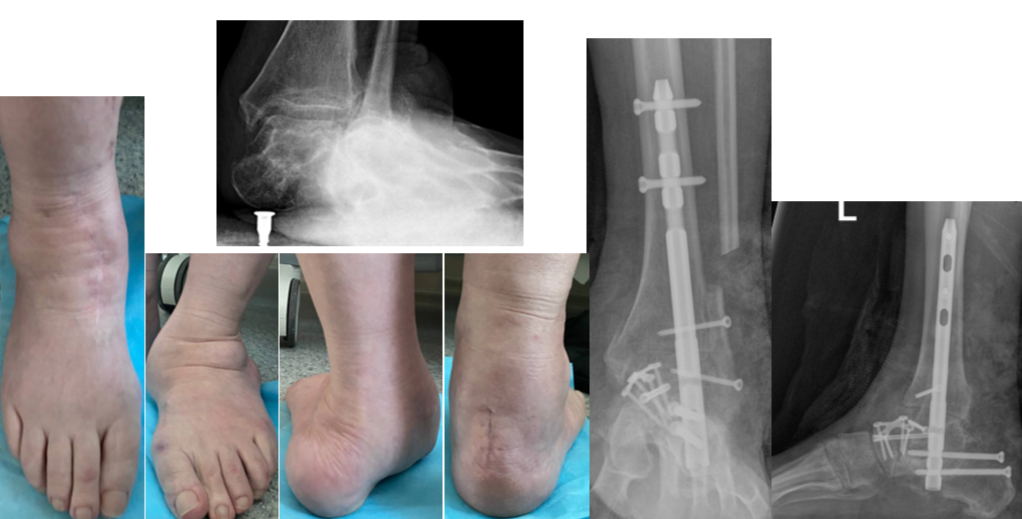

«Я жила обычной жизнью: занималась спортом, ходила на каблуках, ездила на машине. Потом постепенно шло искривление стоп, и в последние годы они стали загибаться внутрь. Так сильно, что я передвигалась буквально на костях, было очень больно», — рассказала Ирина.

Как показало обследование, у женщины была запущенная плосковальгусная деформация обеих стоп. Ступни были сильно «завалены» внутрь, суставы смещены. Наиболее частой причиной развития такого состояния становится врожденная слабость связочного аппарата. К этому могут привести и последствия травм, неврологические проблемы, а лишний вес и неудобная обувь лишь усугубляют ситуацию.

Ирина пыталась как-то исправить ситуацию самостоятельно. Женщина носила ортопедические стельки и специальную обувь. Однако на данной стадии проблема была уже анатомической: кости стояли неправильно. Исправить можно было только хирургическим путем.

Операцию разделили на два этапа. Около года назад Ирине провели вмешательство на правой ноге, а в феврале 2026 года — на левой.

«Сначала мы оперируем более пораженную ногу: таков стандарт безопасности. Затем требуется хирургическая пауза, чтобы пациентка восстановилась, научилась ходить на костылях, опираясь на здоровую ногу. Только когда первая стопа уже может служить надежной опорой, мы оперируем вторую. Это минимизирует риски и делает реабилитацию комфортнее», — Сергей Гуди.

Врачи вернули обеим стопам правильное положение и зафиксировали кости при помощи специальных конструкций, чтобы они срослись в нужной позиции. Обе операции прошли успешно, сейчас Ирина восстанавливается.